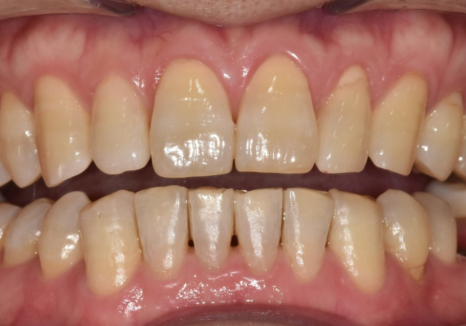

이번 사례의 환자분은

아래 중앙 앞니(#41) 하나가

혼자만 안으로 쑥 들어가 있어

배열이 어긋나 보이는 게

가장 큰 고민이셨습니다.

230613

치아 라인을 위에서 내려다보니

매끄러운 U자 아치형이

앞니로 인해

'ㄷ' 자로 꺾인 모습이었습니다.